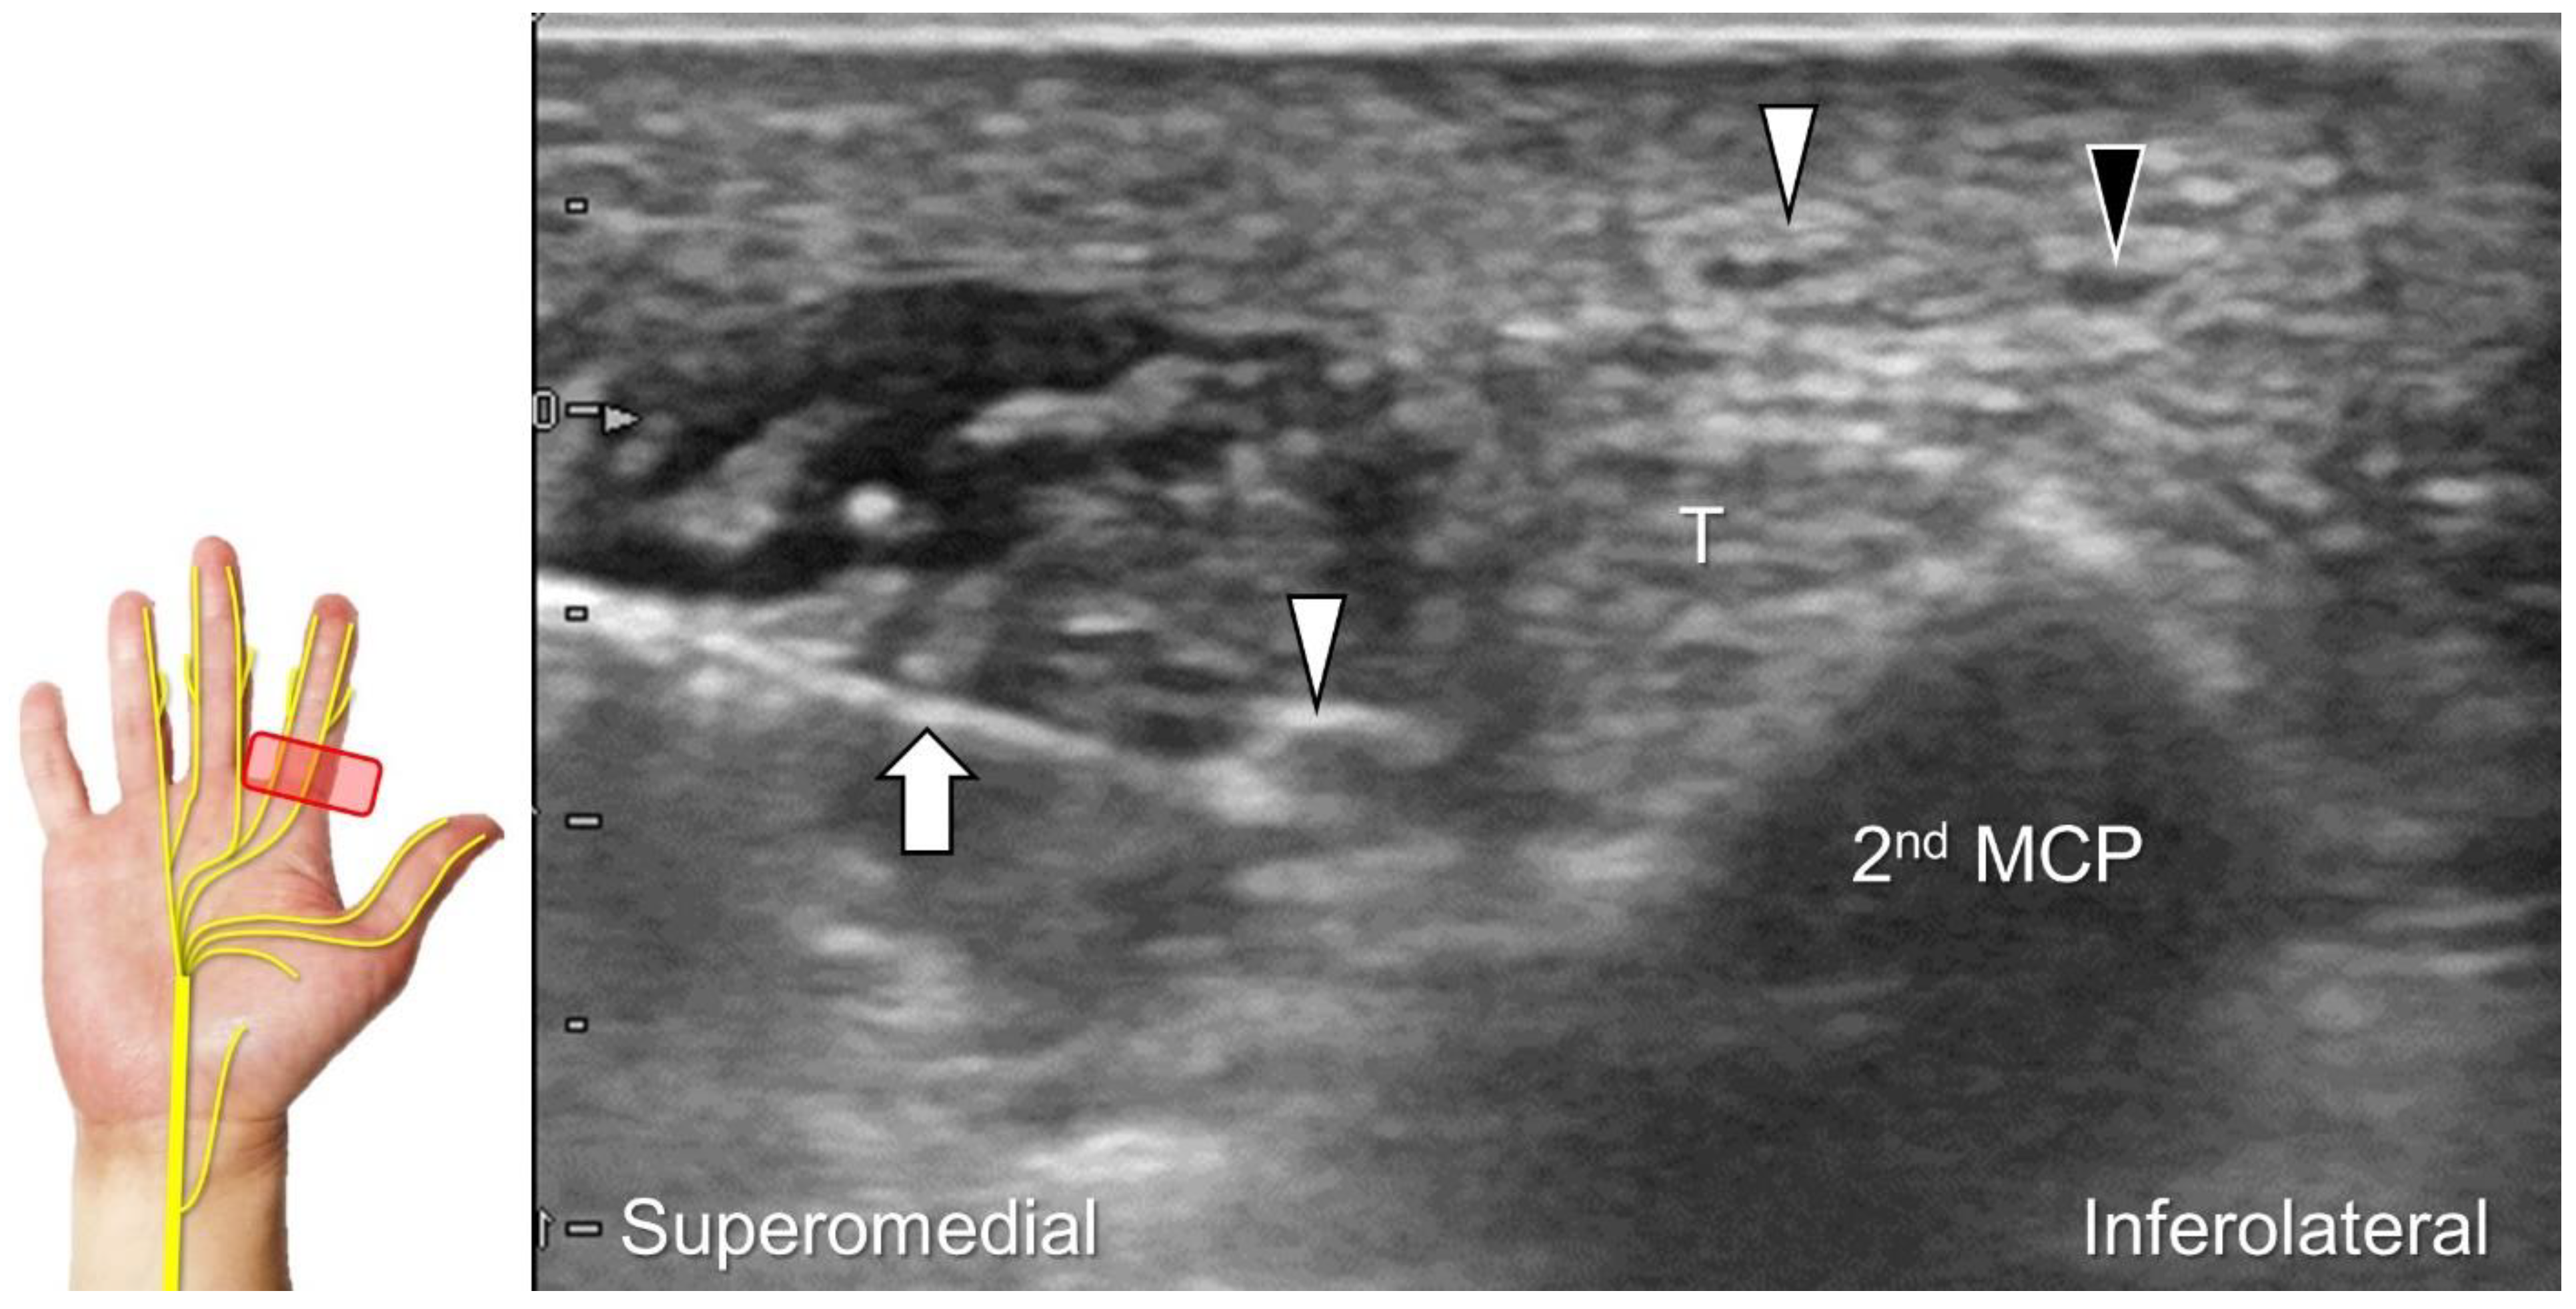

Chronic irritation may lead to the formation of a neuroma, which can occasionally be detected through US imaging (Figure 31). Using the in-plane approach in short-axis view (Figure 32, Video S4), hydrodissection of the entrapped nerves can be performed after identifying the palmar common digital artery and flexor digitorum superficialis/profundus tendons.

Figure 32. In-plane ulnar to radial approach is used for injecting the palmar common digital nerve in short-axis view. White arrowheads: palmar common digital nerve; black arrowhead: common palmar digital artery; arrow: needle; T: flexor tendons; 2nd MCP: second metacarpal.